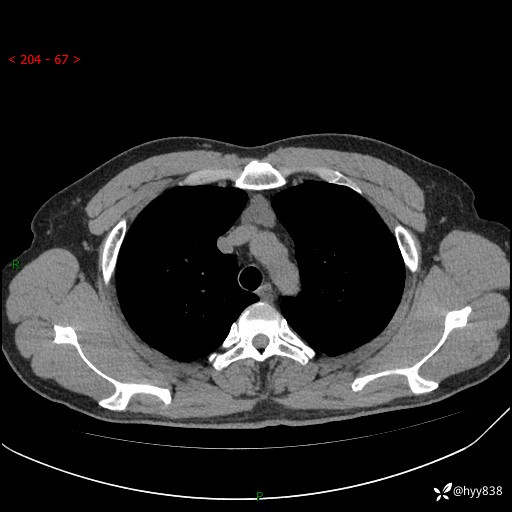

患者性别:女

患者年龄:49岁

简要病史:跟骨骨折,常规CT发现纵隔占位

胸部CT平扫

增强(动脉期+静脉期)